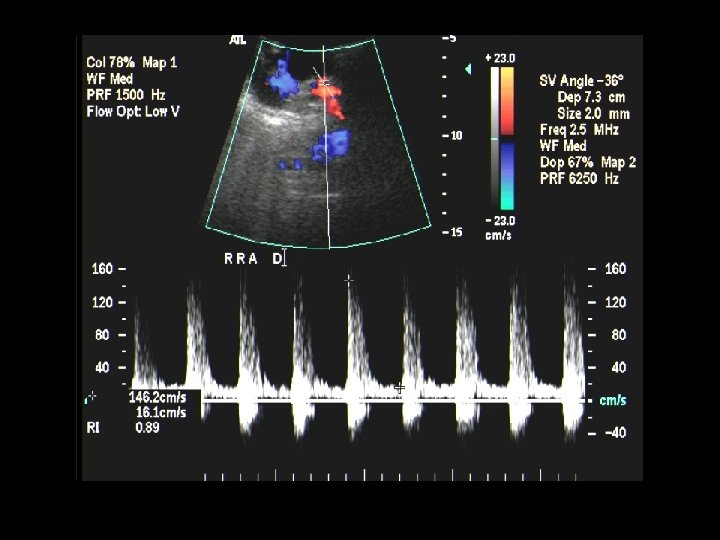

RRA stenosis at origin. Note turbulent flow And increased velocities